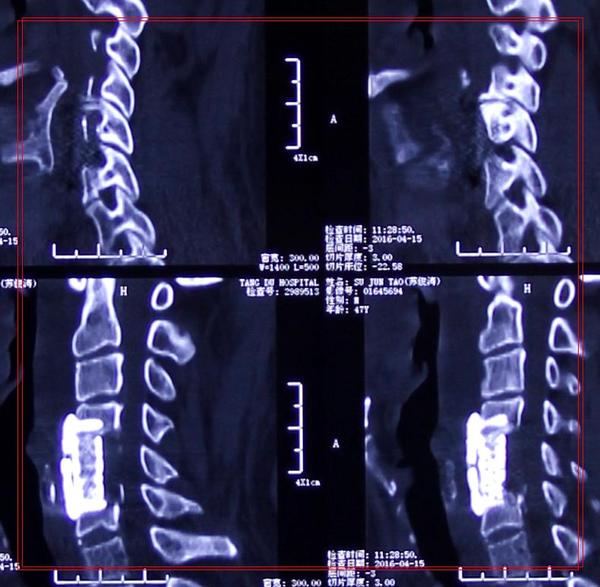

影像学资料